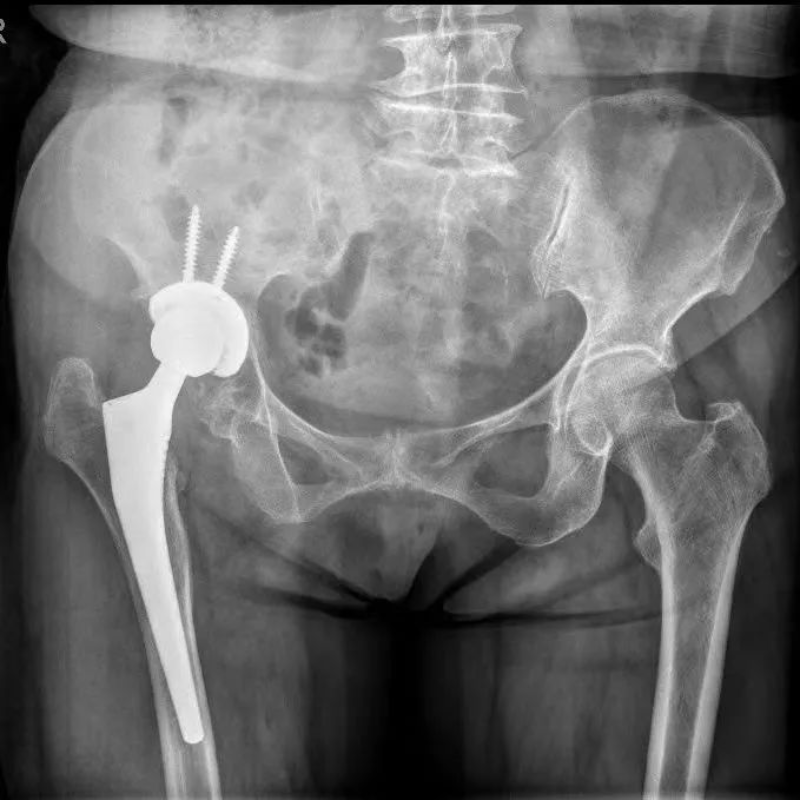

60多岁的谢阿姨,年轻时因为外伤造成右侧髋关节活动受限,因为各种原因一直未得到良好的诊治,就这样右腿“瘸”了近40年,而且走起路来越来越疼。因为走路不平衡,造成了腰椎也弯曲畸形了。经过多方寻诊找到了我院骨创伤与关节外科陈天实主任,通过了解知道惠州市中心人民医院中文博彩平台分院骨关节科可以完成此类手术,便下定决心住院等待手术。完善术前各项检查后,谢阿姨的指标满足手术条件。畸形了近40年的右髋关节给手术医生提出了挑战,但通过AI策划,将复杂的骨骼形态分析处理,给出了适合的手术方案,并通过数据模拟演示了关节假体需要安放的位置和角度,大大减轻了术前规划的工作量。通过陈天实主任手术团队和麻醉科手术室团队的紧密配合下,谢阿姨的手术顺利完成。术后3天谢阿姨便扶着助行器下地走路了,家里人都说:“早知道这么好效果,我们早点带她来做手术了。”术后一个月,谢阿姨已经可以在家做家务帮忙带小孩子了。

△术后